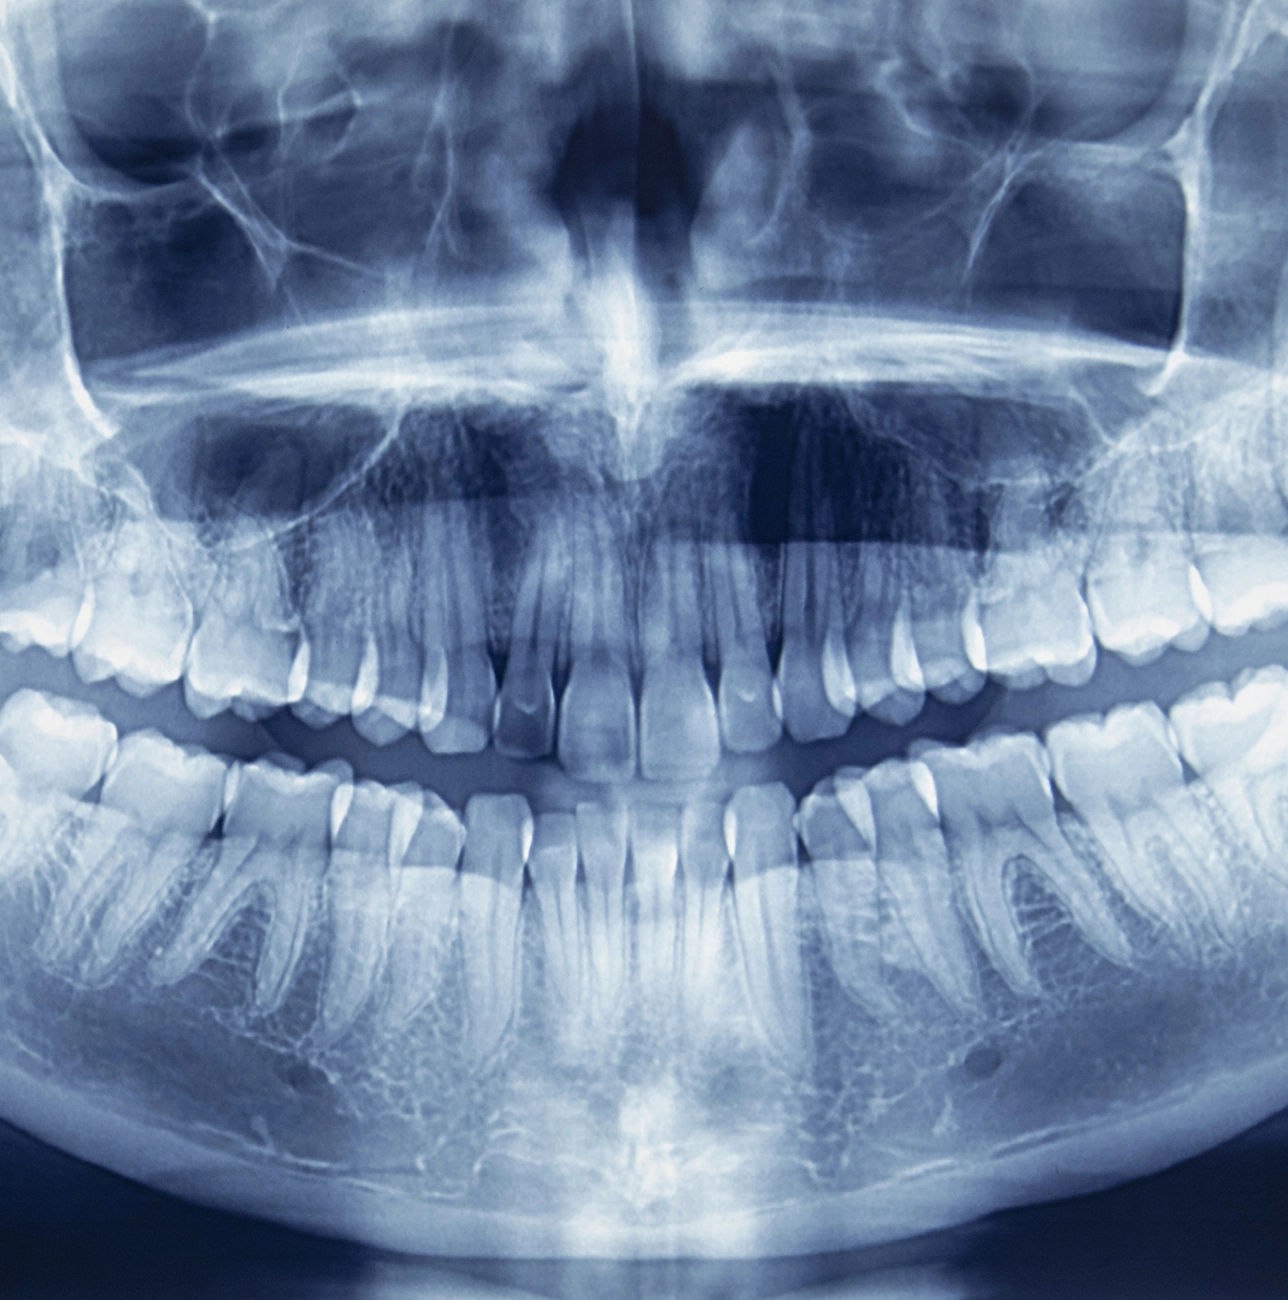

Riconoscere per tempo i danni grazie alle radiografie

Le radiografie aiutano a individuare per tempo eventuali danni ai denti e di conseguenza sono uno strumento indispensabile per fare una diagnosi e per pianificare un trattamento.

Molti danni ai denti e ai tessuti del cavo orale hanno origine in punti nascosti. A occhio nudo è praticamente impossibile valutare lo stato degli spazi interdentali e delle parti dei denti e delle ossa ricoperte dalla gengiva. Grazie alle radiografie, invece, il dentista riesce a individuare per tempo eventuali problemi. Per questo motivo, le radiografie sono uno strumento indispensabile per fare una diagnosi e per pianificare un trattamento, oltre a essere fondamentali per la documentazione del medico dentista.

In odontoiatria vengono utilizzate svariate tecniche radiologiche, che vanno dalla radiografia di singoli denti alla tomografia tridimensionale dei denti, della mascella o della mandibola.